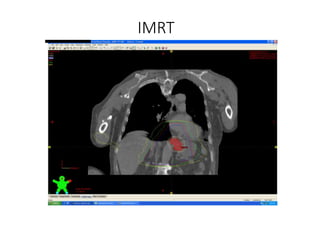

IMRT

• Intensity Modulated Radiation Therapy

IMRT in Esophageal Cancer

• With the exception of a small series that used IMRT

to treat patients with cervical esophageal primaries,

most data regarding IMRT for esophageal

malignancies has been limited to dosimetric

analyses

• found superior to 3dcrt in generating more

conformal and homogeneous target coverage

• Reducing dose to Spinal cord, Heart Lung

3 D vs. IMRT